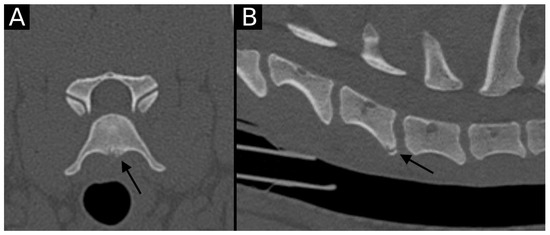

The junction between the endplates and intervertebral discs of the cervicothoracic junction (C6–C7, C7–T1 and T1–T2) were evaluated for the presence of alterations. When present, they were also graded and scored for EPJA, IVD herniation, spondylosis deformans, endplate sclerosis, articular process joint osteoarthrosis, and the presence of vertebral morphological abnormalities. The scoring system for endplate junction alterations and other spinal abnormalities was based on the proposed scoring by Tellegen et al. [13] for presumed EPJF at the lumbosacral spine. Endplate junction alterations were classified into four types (A, B, C, D): Type A involved presence of irregularity of the endplate margins without an obvious free fragment (Figure 1 and Figure 2); Type B involved avulsion evidenced by a thin rim of bone associated with a defect in the dorsal edge of the adjacent endplate (Figure 3); Type C included frank avulsion of a bony fragment (Figure 4) and Type D included presence of bony avulsion of both endplates. If EPJA was present, location (dorsal or ventral) and lateralization of the defect were also recorded. IVD herniation was graded from grades 0 to 3: grade 0 indicated no to mild (0–24%) herniation; grade 1 indicated mild to moderate (25–49%) herniation; grade 2 indicated moderate to marked (50–74%) herniation; grade 3 indicated marked herniation to complete obliteration (75–100%) of the vertebral canal by disc material. Spondylosis deformans was scored from grades 0 to 3: grade 0 indicated no enthesophytes; grade 1 indicated a small enthesophyte at the edge of the epiphysis that does not extend past the endplate; grade 2 indicated the presence of an enthesophyte that extends beyond the endplate but does not connect to the adjacent vertebra; and grade 3 indicated connecting enthesophytes from adjacent vertebrae forming a mineralized bridge. The other mentioned abnormalities (IVD mineralization, endplate sclerosis and articular process joint osteoarthrosis) were scored as present (1) or absent (0).

Figure 1. Transverse (A) and sagittal (B) reconstructions in bone algorithm. An irregular contour surrounded by mild sclerosis (arrow) is observed at the ventral aspect of the C6 caudal endplate, consistent with EPJA Type A. Mild spondylosis deformans is observed in the same vertebra.